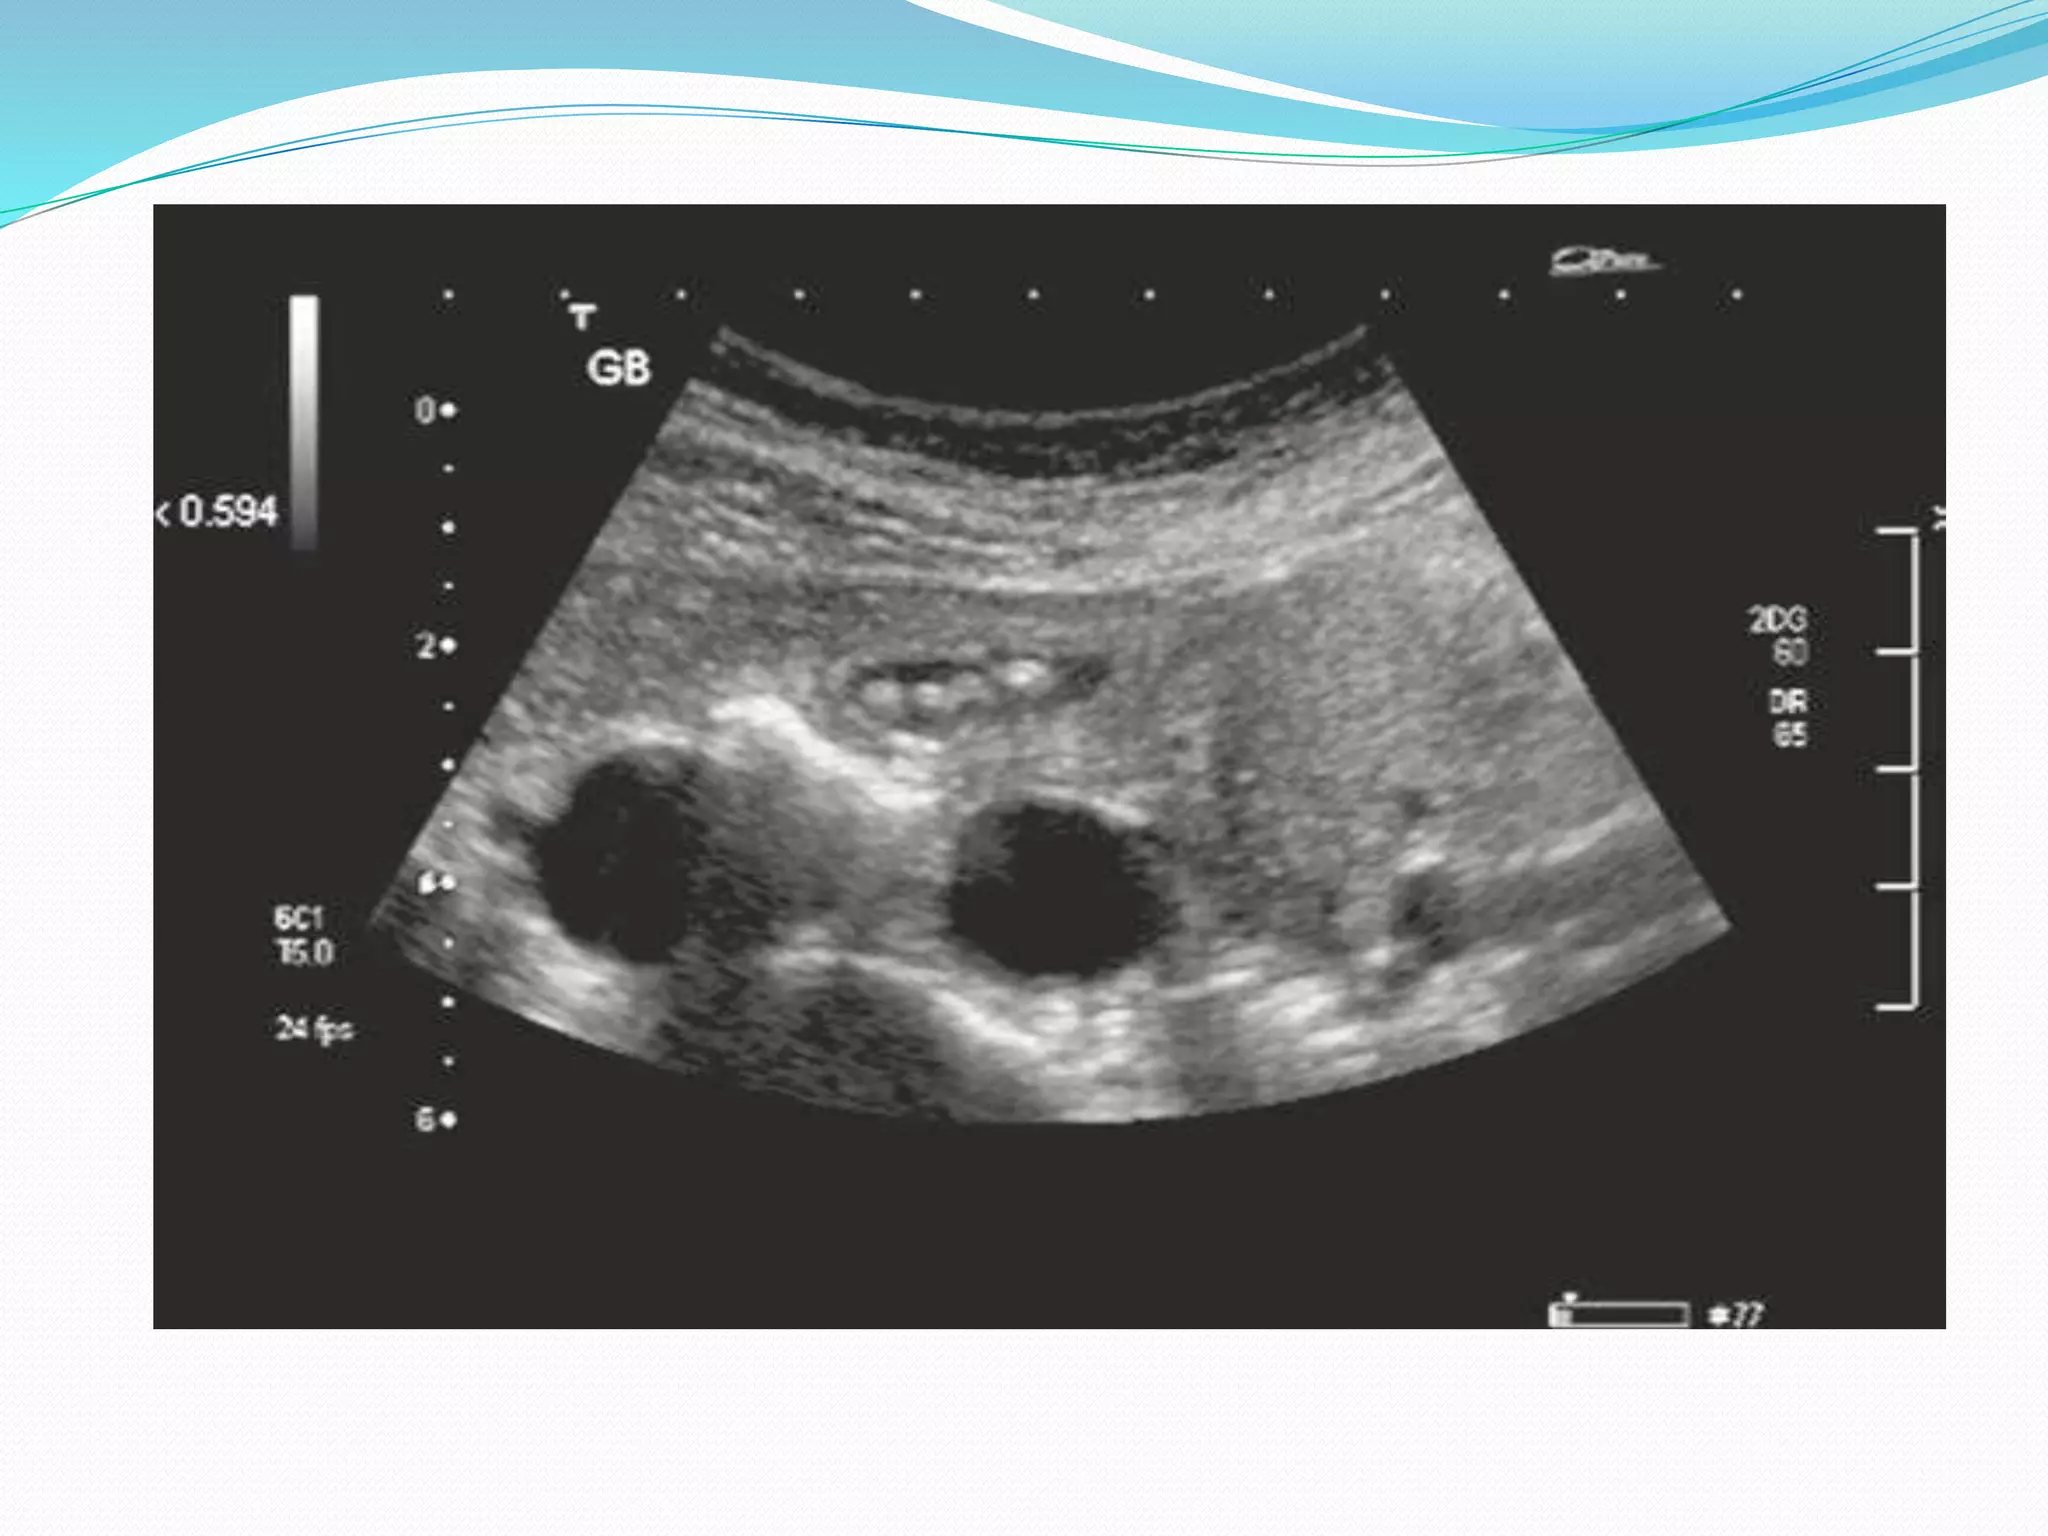

ABDOMINAL ULTRASONOGRAPHY

* Is the initial imaging modality of choice as

- it is accurate

- readily available

- quick to perform

- inexpensive

OPERATOR DEPENDANT AND MAY GIVE SUBOPTIMAL RESULTS DUE TO

EXCESSIVE BODY FAT AND BOWEL GAS

* Biliary obstruction is characterized by BILIARY DILATATION

THIS DILATATION MAY BE CONSPICUOUSLY ABSENT IN 15 % OF

PATIENTS

* Prospective evaluation of USG suggests that level of obstruction can be

defined in 90 % of the cases

* COLOR FLOW DOPPLER SONOGRAPHY may assist in distinguishing dilated

ducts from Portal venous and Hepatic arterial branches

* Provides useful information about the nature and etiology of BILIARY

OBSTRUCTION

* Mass lesion visualization is possible

THE RELIABILITY WITH WHICH A BENIGN DISEASE MAY BE

DISTINGUISHED FROM A MALIGNANT PROCESS REMAINS UNCLEAR

*Upper limits of normal diameter of

CBD-8mm

CHD-6mm